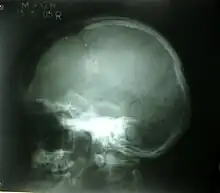

Skull fracture

A skull fracture is a break in one or more of the eight bones that form the cranial portion of the skull, usually occurring as a result of blunt force trauma. If the force of the impact is excessive, the bone may fracture at or near the site of the impact and cause damage to the underlying structures within the skull such as the membranes, blood vessels, and brain.

There are four major types of skull fractures: linear, depressed, diastatic, and basilar. Linear fractures are the most common, and usually require no intervention for the fracture itself. Depressed fractures are usually comminuted, with broken portions of bone displaced inward—and may require surgical intervention to repair underlying tissue damage. Diastatic fractures widen the sutures of the skull and usually affect children under three. Basilar fractures are in the bones at the base of the skull.